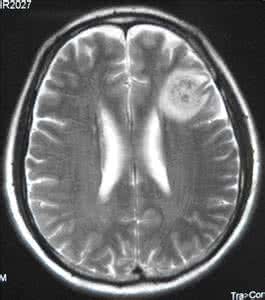

非小细胞肺癌脑转移患者预后非常不好,如果不进行治疗,平均生存时间1-2个月。近年来靶向治疗在非小细胞肺癌治疗中贡献良多,那我们今天就来了解一下常见靶向药对肺癌脑转移的疗效如何。